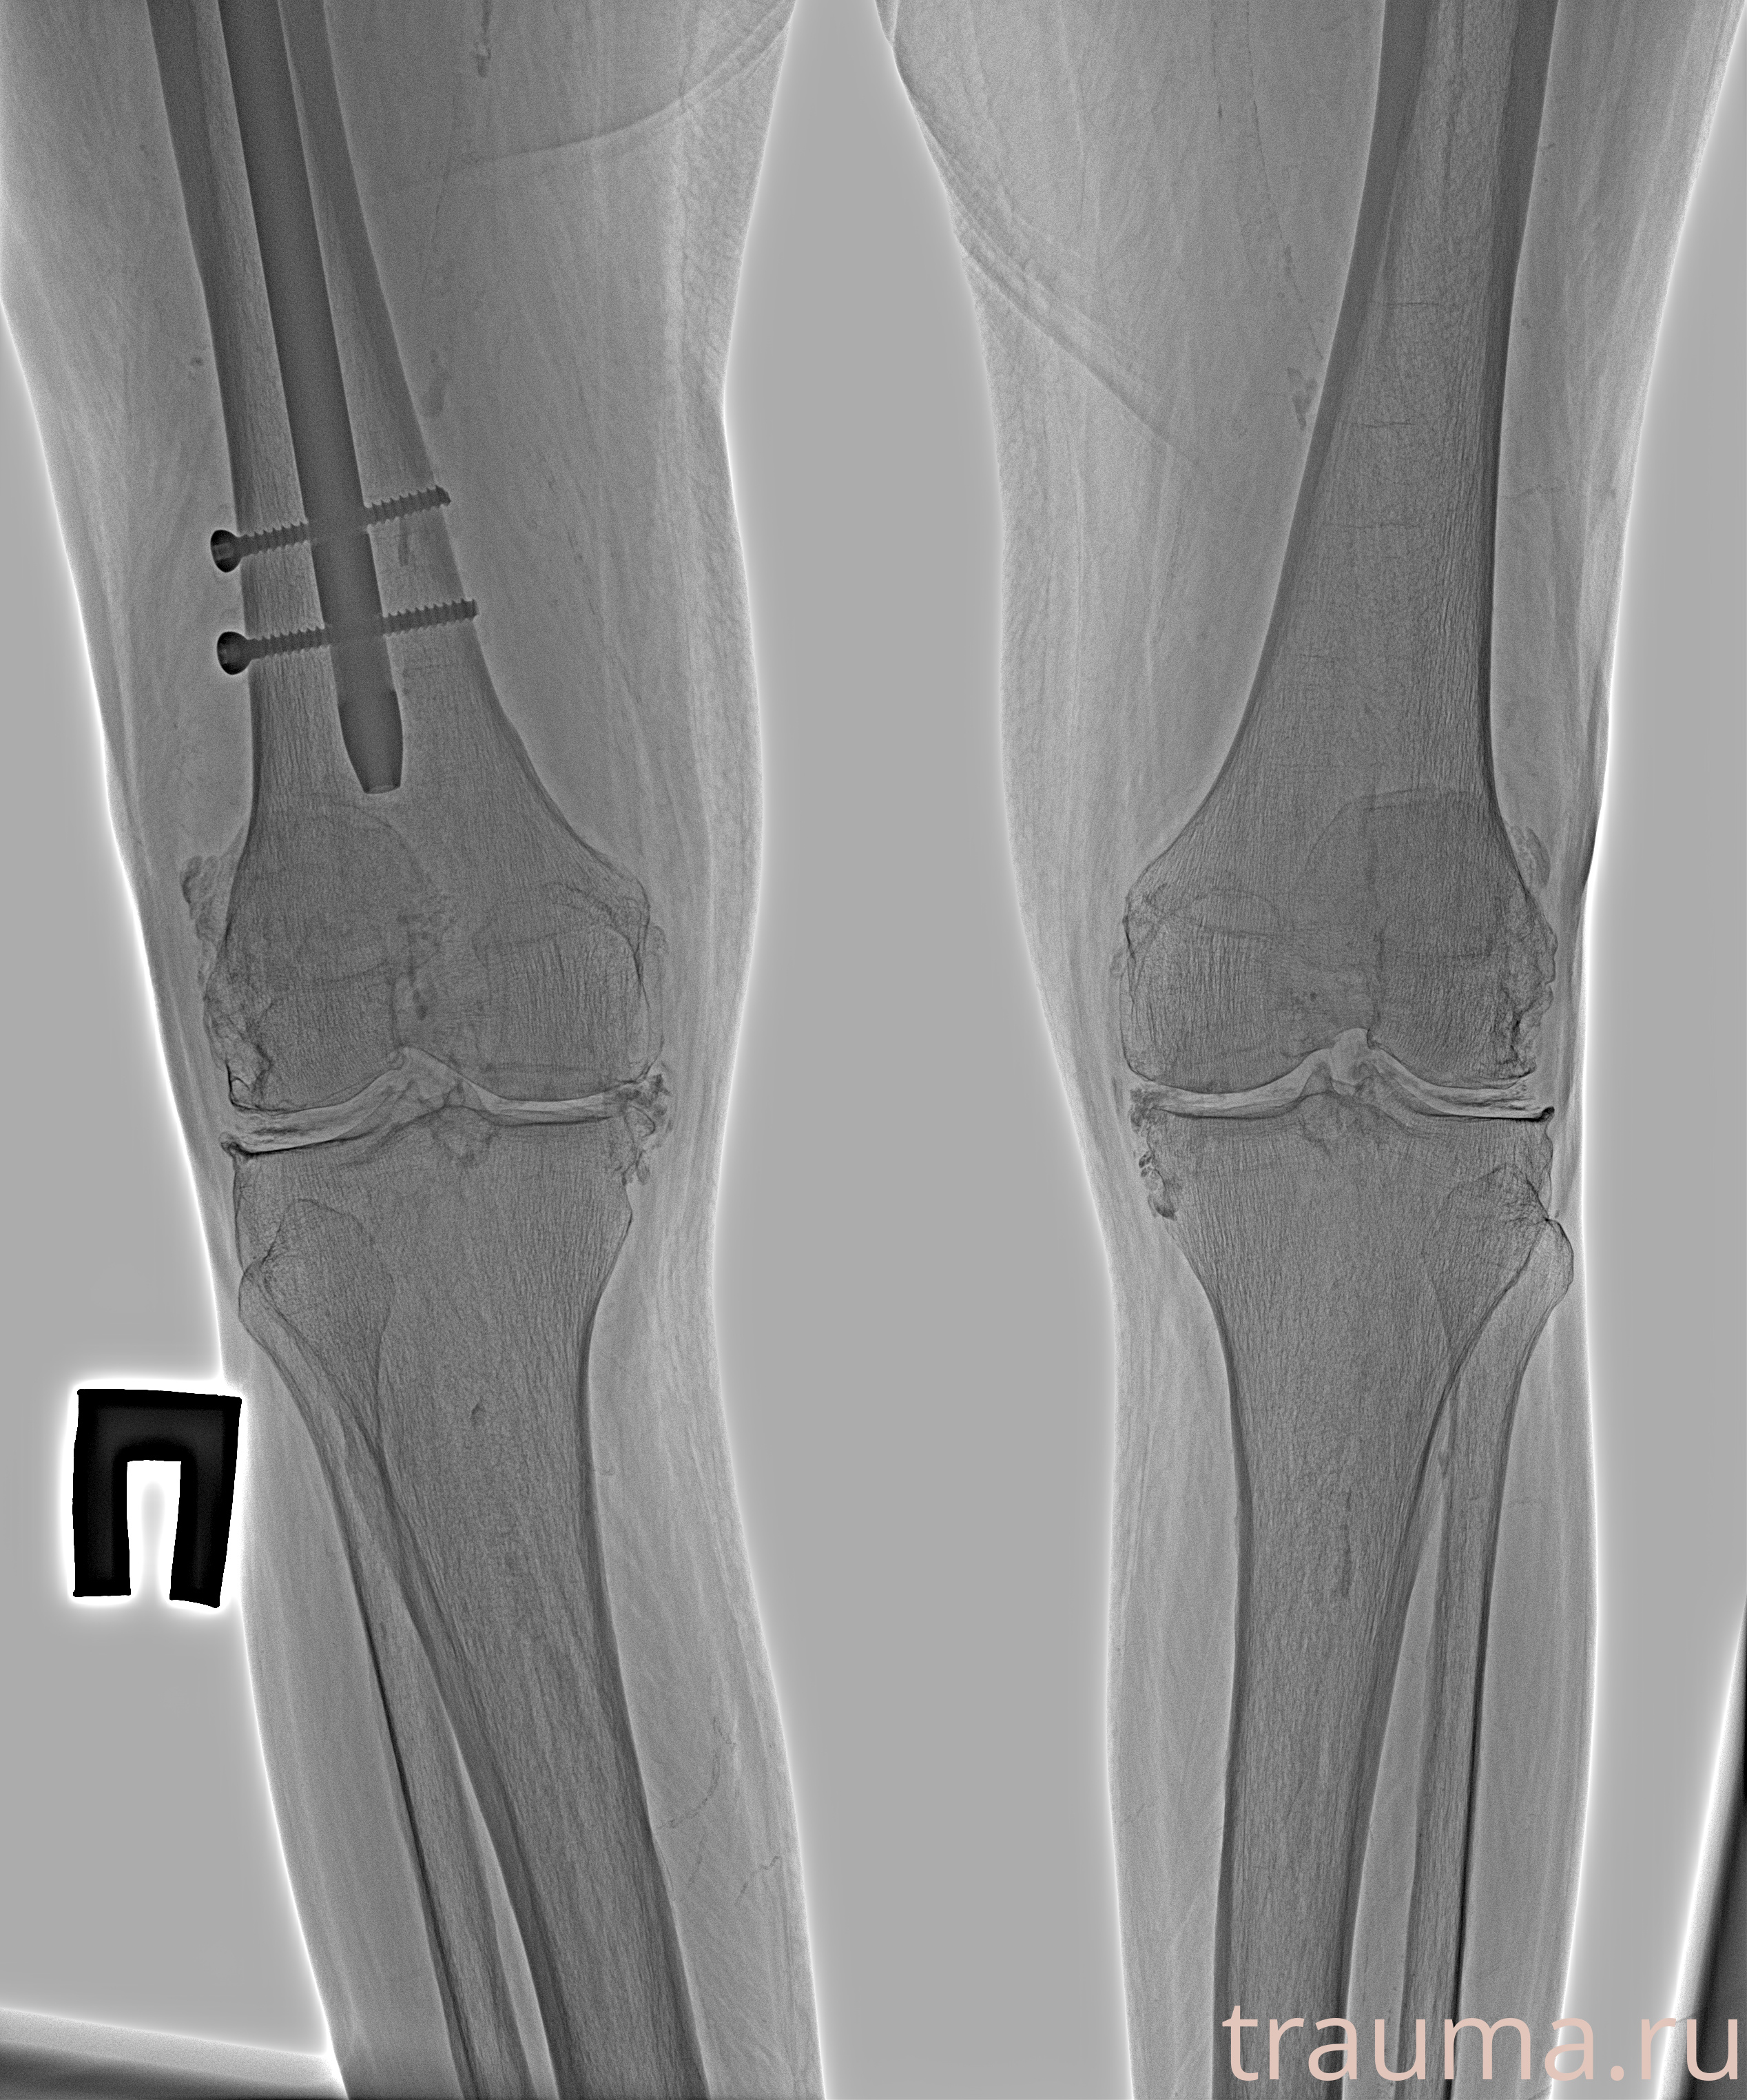

Рентген на дому: по вашему адресу приезжает врач-рентгенолог, травматолог-ортопед с мобильным рентгеновским аппаратом, проводит диагностику травмы или заболевания, делает необходимые рентгенограммы, дает рекомендации по дальнейшему лечению. Получить качественные снимки в домашних условиях возможно благодаря уникальной методике, разработанной МосРентген Центром для института  Склифосовского